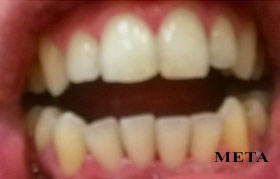

PHOTO GALLERY